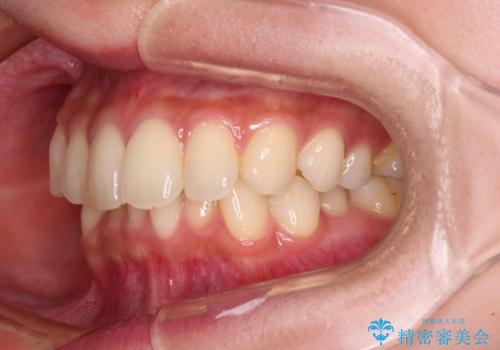

- 前歯のデコボコと強い咬みしめを気にして来院された患者様です。

インビザラインを用いて、前歯の叢生を解消するとともに、ディープバイトを改善していくこととしました。

海外へ転居する予定があったため、1日22時間以上の装着時間をしっかりと守っていただき、予定期間よりも早く、思っていた以上にきれいに仕上げることができました。